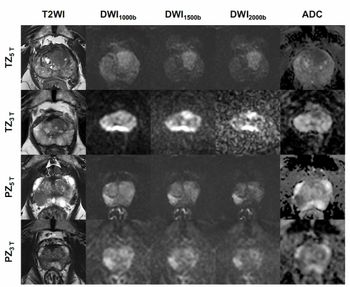

From November 2005 to September 2007, deSouza and colleagues prospectively enrolled 59 women, aged 24 to 83, who underwent T2-weighted imaging and DWI with a specially designed intravaginal coil.

Subjects were assigned to one of two groups. Group 1 comprised women with abnormal screening results waiting for a biopsy. Group 2 was made up of women with incomplete resection of biopsy-confirmed Ia or Ib1 invasive cervical carcinomas or suspicious but ambivalent biopsy results.

As reported in the November 2008 issue of the journal Radiology (2008;249:541-550), investigators found water diffusion was significantly reduced in cancerous tissue compared with normal tissue (p<.0001).

DWI enabled researchers to differentiate cervical cancers from the normal glandular lining of the cervix. Use of these measurements, in combination with the standard MRI sequences, makes detection of early-stage cervical cancer easier, deSouza said.